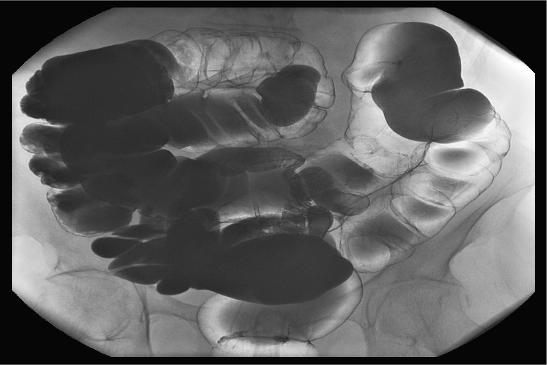

Röntgen von Magen oder Darm

Eine Übersichtsaufnahme des Bauchraumes mittels Röntgen auch Abdomen-Übersichtsaufnahme genannt – ist eine bildgebende Untersuchungsmethode. Sie kann Ärztinnen und Ärzten erste Hinweise für krankhafte Prozesse wie einen Darmverschluss geben.

Röntgenuntersuchungen des Magen-Darm-Trakts mittels Kontrastmittel können weitere Informationen zur Funktion von Magen bzw. Darm liefern, zum Beispiel zur Beurteilung der Beweglichkeit des Darms. Allerdings sind zur eindeutigen Diagnostik Untersuchungen wie Ultraschall, CT, MRT sowie Endoskopie die gängigsten Untersuchungsmethoden. Ihre Ärztin oder Ihr Arzt klärt Sie über die Möglichkeiten der Diagnose bzw. Untersuchungen auf. Diese richten sich unter anderem auch nach dem Grund der Untersuchung bzw. Verdachtsdiagnose.